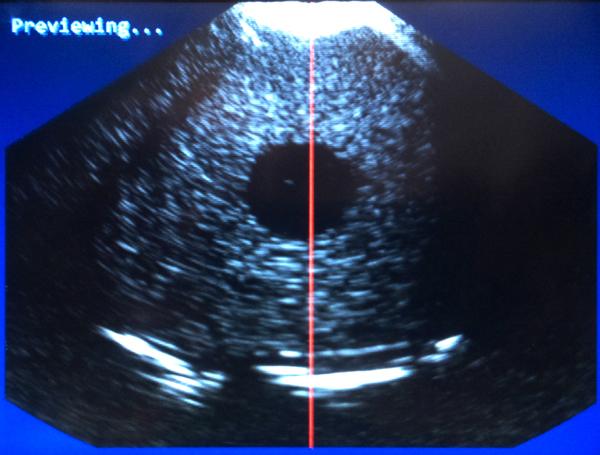

CareScan -1échographe de la vessie , développé par WellEcho , était le fruit d'années de recherche et développement . Le produit utilise une nouvelle génération de l'imagerie et de la technologie de sondage qui est complètement différente de la technologie traditionnelle et est facile à utiliser avec une précision de mesure très élevée.

Avantages du produit - Algorithme plus avancée, la technologie de reconnaissance paroi de la vessie plus puissante , la technologie plus précise des contours, une plus grande précision de la sonde rend résultats d'analyse plus précis. - Nouvel algorithme , les résultats des mesures ne sont pas soumis à la forme et taille de la vessie. Pas besoin de sélectionner le sexe, groupe d'âge et le pas besoin d'examiner des cas particuliers tels que l'effet de l'hystérectomie sur les résultats de mesure. Bonne compatibilité des différents vessies, aucune erreur importante lorsque la mesure de petites vessies ou vessies de forme spéciale , facile à utiliser - Taux de reconnaissance élevé pour la paroi de la vessie avec de l'air , la quantité précise du volume d'urine , même quand la vessie n'est pas complètement remplie. - Avec les fonctions manuelles de contour, lorsque Contour automatique est vraiment difficile , cela peut être contourné manuellement via l'écran tactile, afin de s'assurer que les résultats précis peuvent être obtenus même si la frontière de la vessie est anormal. - L'imagerie en temps réel pendant le processus d'analyse, de surveillance en temps réel de l'insertion du cathéter afin de mieux prévenir la douleur causée par l'insertion inapproprié. -10ml ~ 2000ml grande plage de mesure - La sonde utilise un nouveau moteur pas à pas en trois dimensions, peut maintenir durablement la numérisation de haute précision, étalonnage périodique n'est pas nécessaire. -Paramètres identifiables à l'intérieur de la sonde, la sonde peut être rapidement remplacé sans l'étalonnage secondaire. - Built-in 24Wh grande capacité de la batterie , le temps de travail continu > 4 heures, la batterie peut être rapidement remplacé . - Le fonctionnement de l'écran tactile , les menus simples, faciles et rapides à utiliser . - Compact et léger, facile à transporter.

Application: Scanner de la vessie est utilisée pour visualiser, suivre et mesurer de manière non invasive le volume d'urine dans la vessie, afin de déterminer si d'uriner est nécessaire et le débit urinaire et pour éviter une insertion inappropriée du cathéter dans la vessie. Scanner de la vessie est largement utilisé en urologie, la réadaptation, la chirurgie, salle d'opération et les soins de santé à domicile. Avantages de la numérisation de la vessie • Calcule le volume de la vessie et le résidu postmictionnel • Évite les sondages non nécessaires et l'inconfort du patient • Diminue les risques d’infection des voies urinaires • Surveiller la vessie non invasif pour éviter la rétention urinaire • Surveiller la récupération post-opératoire • Réduit les coûts hospitaliers (jetables) • Favorise l'efficacité du personnel et nécessite peu de formation.